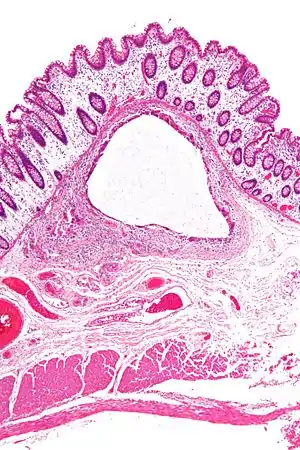

Low magnification micrograph of pneumatosis intestinalis in bowel wall.